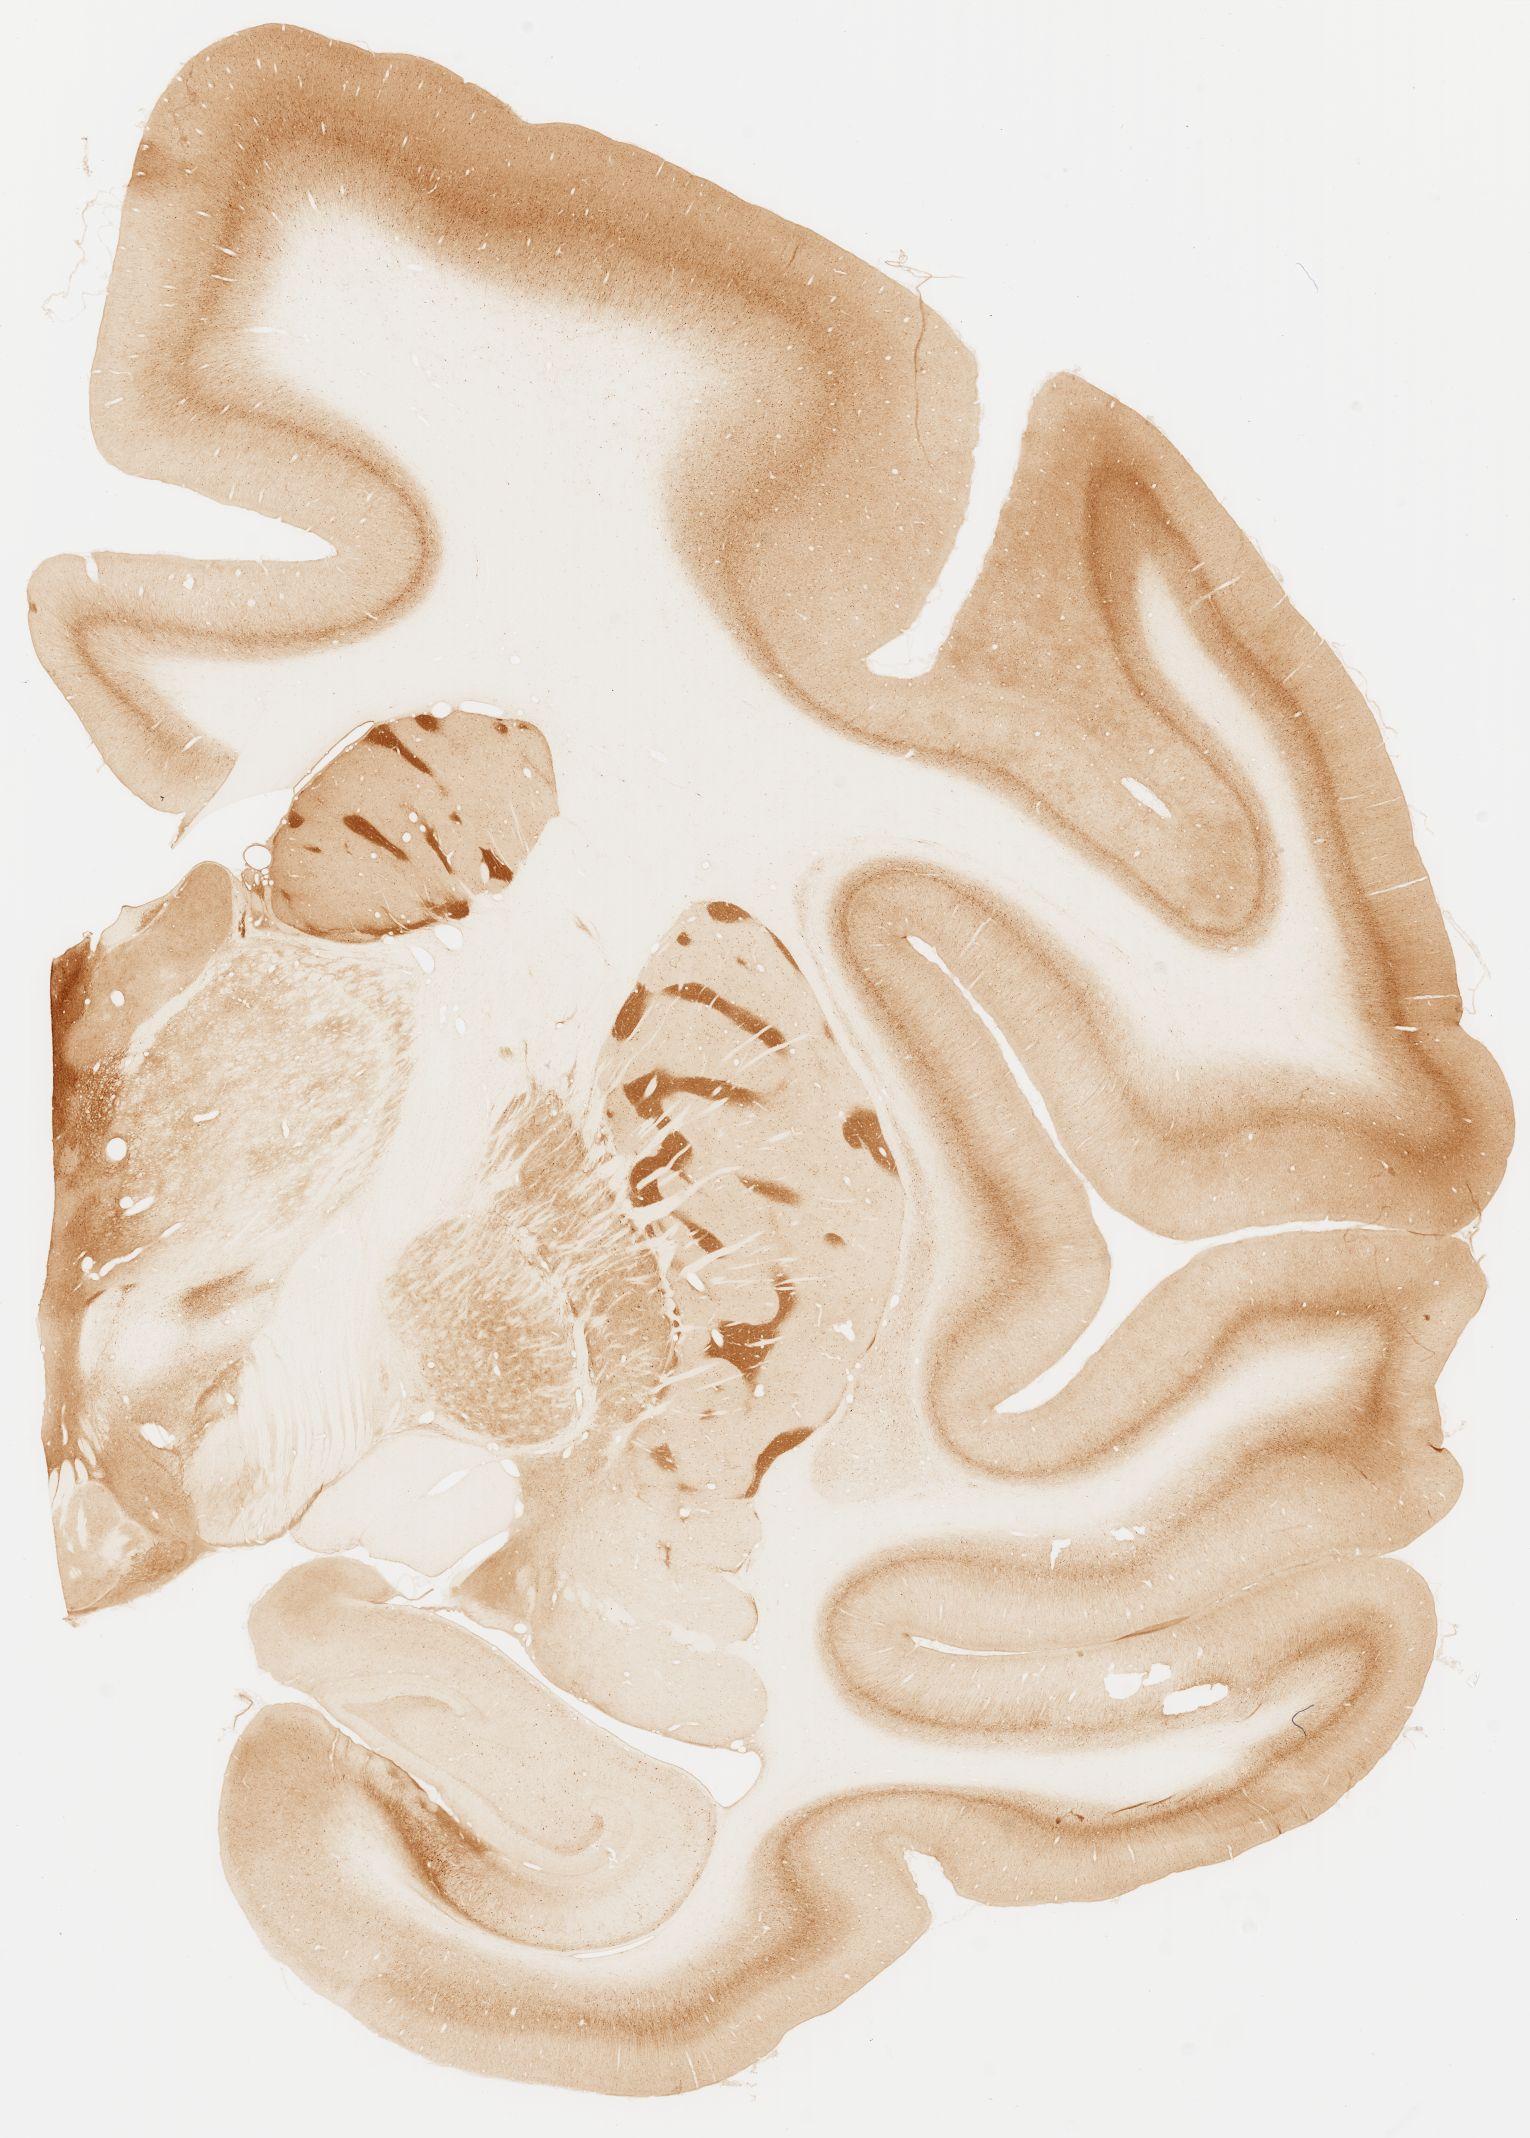

Datasets -> Macaca Fascicularis -> KChIP1, (Potassium Voltage-Gated Channel-Interacting Protein 1), coronal, immuno, Whole-Brain, adult

[ Metadata ]   ·   Source: Edward G. Jones

Displaying Sections 41 thru 80 of 92 Sections for this Dataset